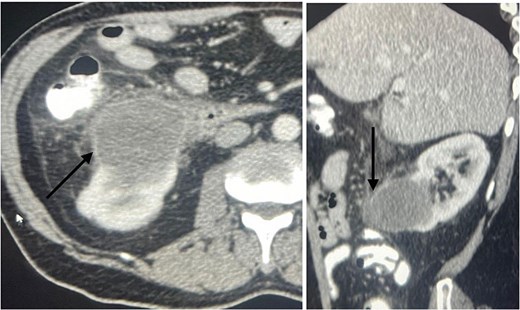

A 60-year-old male patient was referred to our clinic due to concern of infected renal cyst. Five months prior to referral, he underwent an open appendectomy and right limited hemicolectomy due to perforated appendix. At that time he was found to have accidental right Bosniak IIF renal cyst on CT scan and follow up every 6 months was recommended by urologist. Four months later, he came to emergency department with fever, chills and right flank pain. CT scan of the abdomen and pelvis with intravenous contrast was done and showed same size exophytic cyst in the lower portion of the right kidney measuring 4.9 × 5.2 cm but with new finding of rim enhancement with surrounding fat stranding suggesting complicated cyst with possible abscess formation. There was fat stranding and wall thickening of the adjacent ascending colon (Fig. 1). These findings couldn’t differentiate between infected cyst and cancer. Due to the high risk of malignancy associated with Bosniak IIF renal cyst and the challenging differential diagnosis, we further discussed the case with radiologist and decision was made to do an magnetic resonance imaging (MRI) with contrast for further evaluation and for better visualization of internal enhancement. Most MRI findings were suggestive of infected cyst. However, diffusion-weighted imaging and apparent diffusion coefficient (DWI-ADC) map showed strong internal restricted diffusion which is not specific to either abscess or tumor. Reaching the diagnosis based solely on these initial imaging findings was challenging. T1 post contrast image revealed fine internal enhancement suggesting more complex lesion than a simple infected renal cyst or abscess, raising suspicion for a neoplastic process (Figs 2 and 3).

An axial view (on the right) and sagittal view (on the left) showing a ring enhancing lower pole cyst (arrow), suggesting infected cyst vs abscess formation.